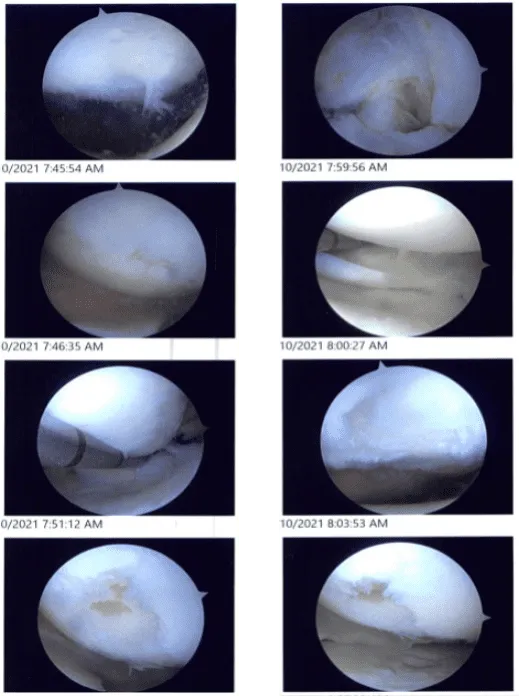

Intraoperative images

Examination of the patellofemoral joint showed a grade I to grade II patellofemoral arthritis. Examination of the medial compartment showed a medial meniscus tear near the root. A medical entry portal was made with the use of a spinal needle. The probe was inserted to further examine.

The medial meniscus root was found to be intact. The shaver was used to shave the root with the use of a straight biter and bitters to do a meniscectomy of the medial meniscus.

The osteochondral lesion of the medial femoral condyle was debrided with the use of a shaver. The abrasion chondroplasty was performed over the medial femoral condyle.

Examination of the intercondylar notch showed a degenerative ACL, but the ACL was intact. Examination of the lateral femoral condyle showed a radial margin degenerative tear of the lateral meniscus, which was removed with the use of a shaver.

Examination of the patellofemoral compartment showed an osteochondral lesion, which was debrided with the use of a shaver. Final pictures were taken and saved. The knee was thoroughly irrigated and drained.